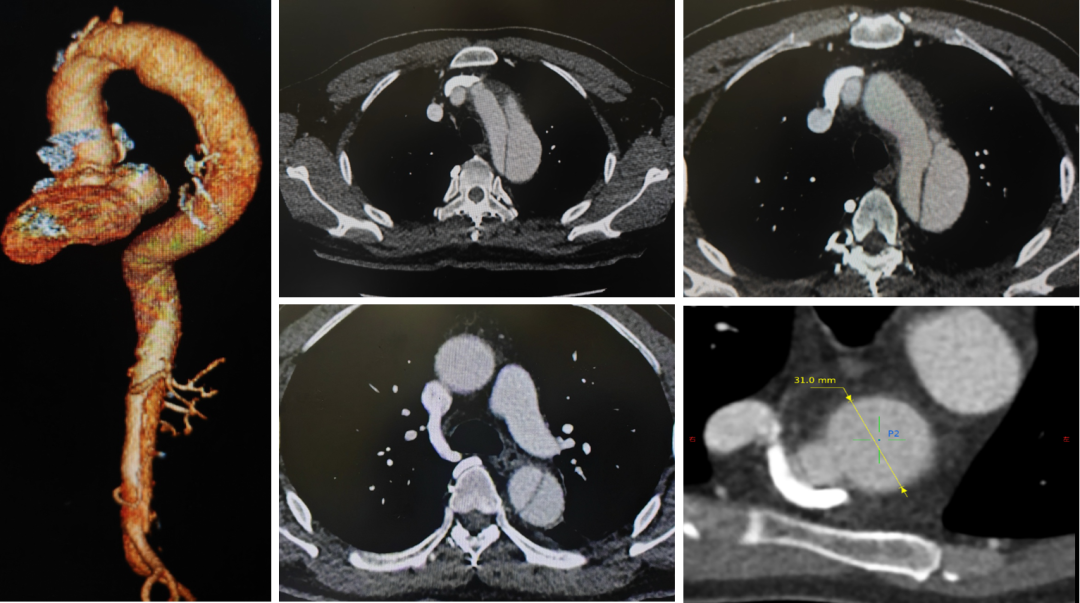

病例二(双开窗)

汪XX,男,52岁,主动脉夹层。LSA、LCCA双开窗。

术前